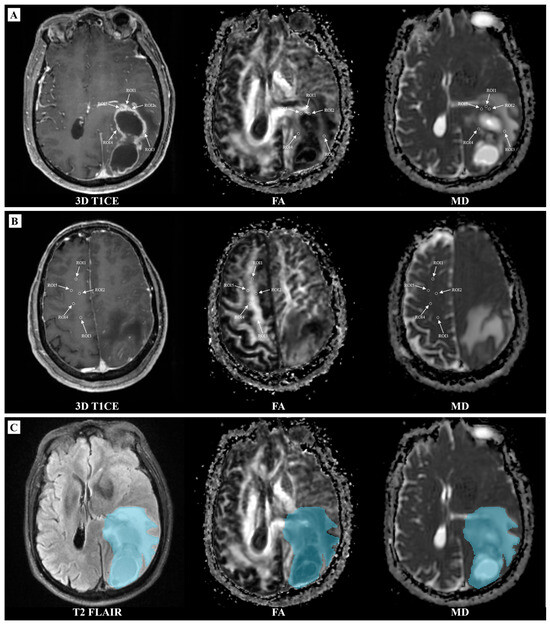

2.3. Imaging Analysis

3.2. Models Development for Predicting IDH

3.3. Models Development for Predicting MGMT